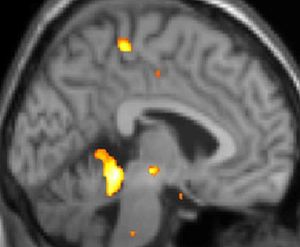

PET 스캔

PET 스캔에 의한, 군발 두통 발생 중에 활발해진 뇌 부분을 나타내는 그림.

양전자 방출 단층 촬영술(PET) 이미지 1: 통증 중 활성화되는 뇌 영역

양전자 방출 단층 촬영술(PET) 이미지 2: 통증 중 활성화되는 뇌 영역

양전자 방출 단층 촬영술(PET) 이미지 3: 통증 중 활성화되는 뇌 영역

실제로 양전자 방출 단층 촬영술(PET) 스캔 연구 결과, 군발 두통 발작 중에 통증이 없을 때와 비교하여 시상하부의 특정 영역이 활성화되는 것이 관찰되었다. 또한, 복셀 기반 형태 계측법(VBM)을 이용한 연구에서는 군발 두통 환자와 그렇지 않은 사람 사이에 뇌 구조를 비교했을 때, 시상하부의 일부 영역에서 구조적인 차이가 발견되기도 했다.[35] 이러한 영상 연구 결과는 시상하부가 군발 두통의 발생과 관련이 깊다는 가설을 뒷받침한다.